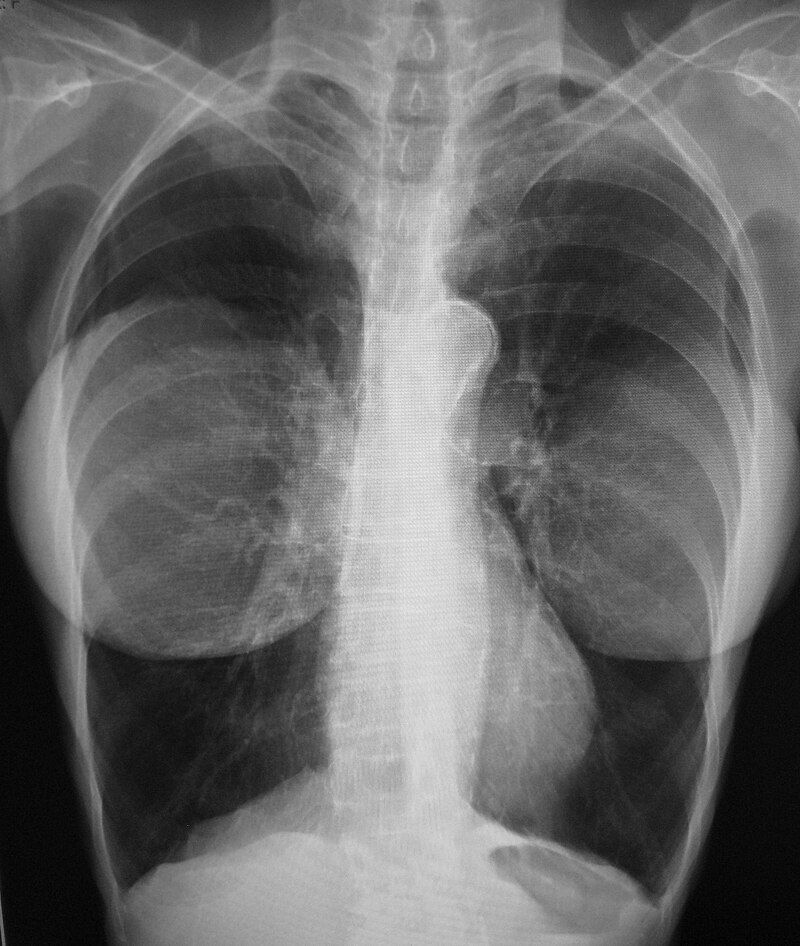

rentgenový snímek ženy s implantáty

Zákrok trval přibližně dvě hodiny a zvětšil její prsa z velikosti „B“ na „céčka“. Operace pak byla veřejně představena na kongresu plastických chirurgů v roce 1963 a hned od příštího roku se začaly implantáty a zvětšování prsou komerčně nabízet. Jejich konstrukce však nebyla zcela bez problémů, přeci jen šlo o novinku. První implantáty měly silné obaly, problematickou se jevila i fixace Dacronem a postupem let se objevily komplikace jako tuhnutí kapsule, bolestivost prsou, objevovala se i migrace gelu nebo rozměrové změny. Sama Timmie ve svých rozhovorech v roce 2012 potvrdila, že první léta nějaké komplikace měla. Přesto si je nechala a i po více než půlstoletí měla stále ty původní a zákroku nelitovala.